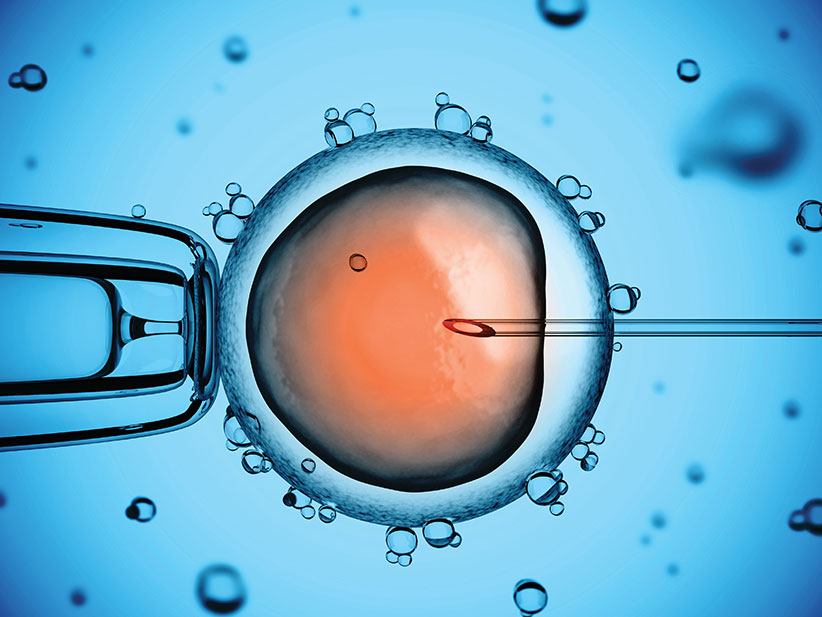

Ин витро е процес, при който се изваждат яйцеклетки от яйчниците на жената, оплождат се от сперматозоиди на мъжа в лабораторни условия, оплодените яйцеклетки се отглеждат няколко дни до развитието на ембриони, които се пренасят в матката на жената.

Публикувано на: 11.04.2009 Какво е ин витро оплождане и ембриотрансфер ?Това е последователен процес, при който се взе...

Публикувано на: 09.01.2007 Ин витро процедурата: Бебе в епруветкаIVF (ин витро) означава фертилизация (оплождане) извън човешко...